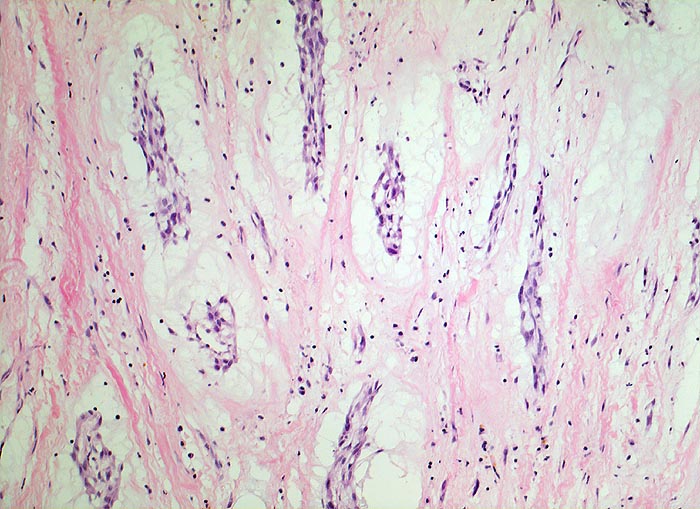

Vorhofmyxom

Stark aufgelockertes teils fibröses, teils myxoides Stroma mit Entzündungszellen und vereinzelten Siderophagen. Darin liegen Nester von spindelförmigen Tumorzellen, die bevorzugt um Gefässe lokalisiert sind.

Histologie

100